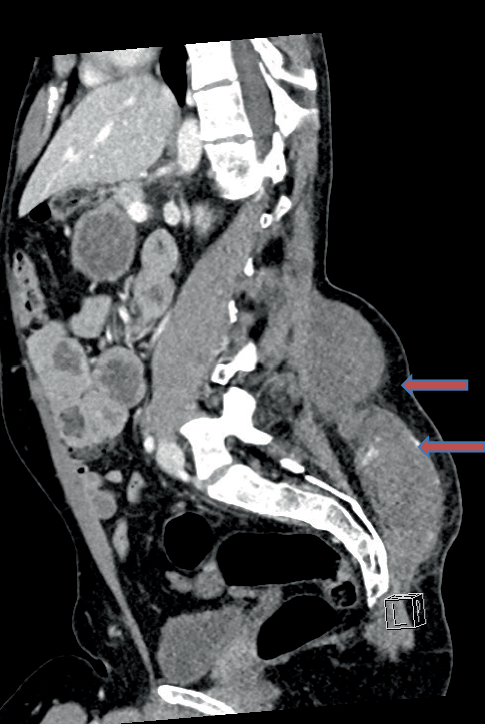

Computed tomography (CT) and CT angiography revealed multiple active arterial bleeding within the subcutaneous tissue at the L5/S1 level, with a large hematoma measuring 18 × 11 cm and 6 cm in depth. Embolization was considered but ultimately not pursued by the interventional radiology team due to distal vessel involvement and a high risk of rupture (Fig. 1).

Fig. 1

Contrast-enhanced sagittal CT scan of the spine and pelvis on admission, demonstrating a large subcutaneous hematoma in the lumbar region. The hematoma extends cranially from the lumbosacral junction and is associated with multiple sites of contrast extravasation (white areas), indicating ongoing active arterial bleeding